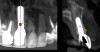

Fig 3. Pretreatment site-specific CBCT showing thick intact buccal plate and class 1 sagittal root position. Preplanning with a bone-level 4.1-mm diameter implant assured a 3-mm buccal gap upon placement and a screw-retained position.

Figure 3

Fig 4. Pretreatment site-specific CBCT showing thick intact buccal plate and class 1 sagittal root position. Preplanning with a bone-level 4.1-mm diameter implant assured a 3-mm buccal gap upon placement and a screw-retained position.

Figure 4

The patient, a healthy 45-year-old nonsmoking woman (American Society of Anesthesiologists [ASA] II), presented with a failed maxillary central incisor due to severe internal-external root resorption (Figure 1). She had a high esthetic risk profile based on 12 presenting esthetic risk factors (key No. 1), including a high lip line, high esthetic expectations, and adjacent teeth that had been restored (Figure 2).Site-specific CBCT (Carestream CS 9300, Carestream Dental, carestream.com) noted a thick intact buccal plate and a class 1 sagittal root position (Figure 3 and Figure 4). Preplanning with a bone-level 4.1-mm diameter x 14-mm long implant (Straumann Bone Level Roxolid® SLActive, Straumann, straumann.com) assured a 3-mm buccal gap upon placement and a screw-retained position (key No. 2). Prior to placement, intact buccal and palatal walls were confirmed. Figure 5 shows palatal wall placement of the implant after minimally traumatic flapless tooth extraction. An anatomically correct surgical guide template was used to assure a screw-retained position and correct vertical depth of approximately 4 mm from the mid-buccal apical extent of the guide template, which correlated to 1 mm apical of the intact buccal plate (key Nos. 3 through 5). The two-unit (8-9x cantilever) fixed provisional was recemented post-surgery. The 3-mm buccal gap was grafted tightly with a low-substitution DBBM (Bio-Oss®, Geistlich Pharma, geistlich-na.com) (key No. 6), and a pouch was created with a Buser membrane instrument (Hu-Friedy, hu-friedy.com) from line angle to line angle as a mini full-thickness flap to the mucogingival border to accept a connective tissue graft (Figure 6). The connective tissue graft, 1-mm thick x 12-mm long x 7-mm wide (Figure 7), was harvested from the palate (key No. 7).